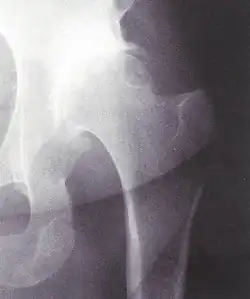

Die dysplasiebedingte Hüftluxation bei Erwachsenen ist eine (unbehandelte) Hypoplasie mit sekundärer Luxation des Hüftgelenks. Der Femurkopf steht nicht im Acetabulum, sondern darüber am Darmbein. Im angelsächsischen Sprachgebrauch wird die Situation als neglected congenital dislocation of the hip bezeichnet – wobei „dislocation“ eigentlich so falsch ist wie „Luxation“.

Zur Diagnose reicht eine Röntgenaufnahme des Beckens. Der radiologische Befund sollte weder mit dem Proximalen Femurdefekt noch mit der (extrem seltenen) teratologischen Luxation verwechselt werden.